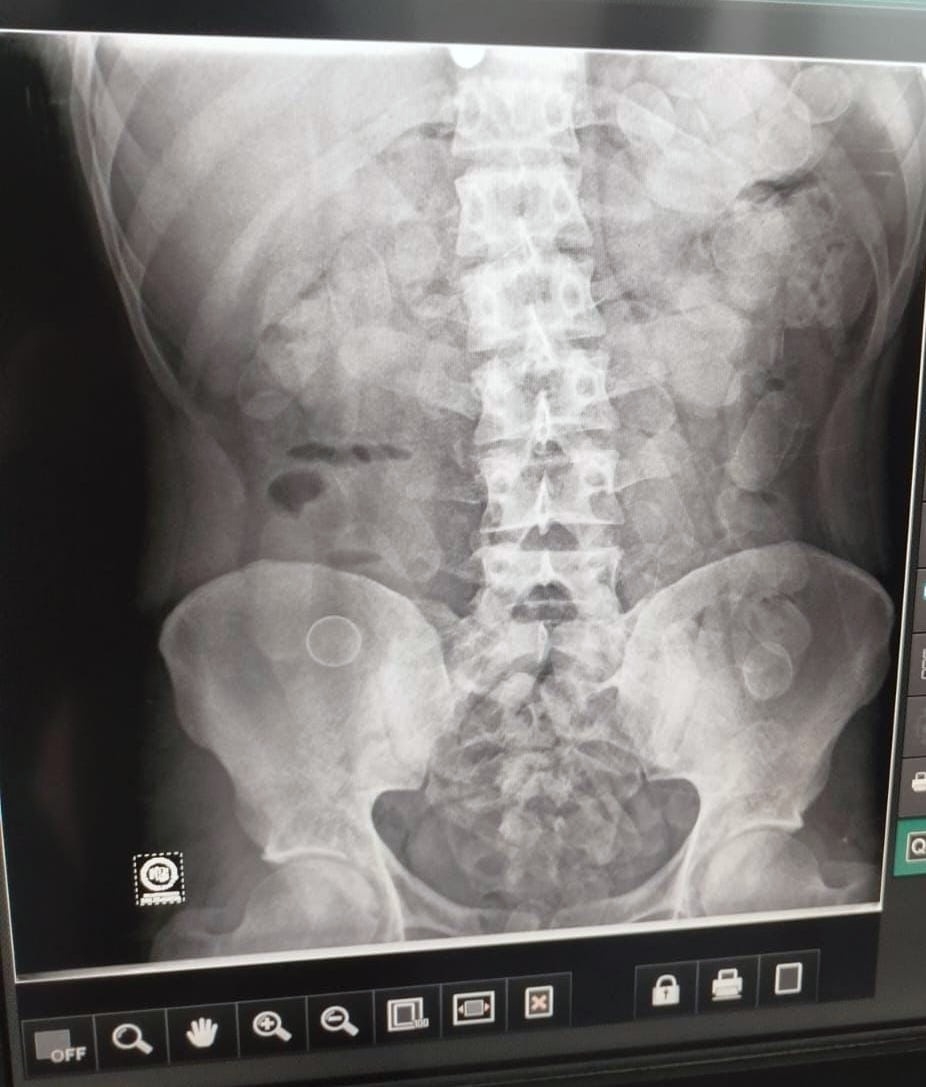

Ante la alerta del can, los gendarmes tomaron contacto inmediato con la Unidad Fiscal Federal de Jujuy, lo que permitió intensificar los controles y trasladar a los involucrados al hospital local. Mediante estudios de Rayos X, se confirmó que ambos poseían cuerpos extraños en sus abdómenes.

Tras la evacuación médica, se constató que los hombres habían ingerido: 95 y 89 cápsulas cada uno. Un total de 184 cápsulas de clorhidrato de cocaína con un peso total de 2 kilos y 168 gramos.